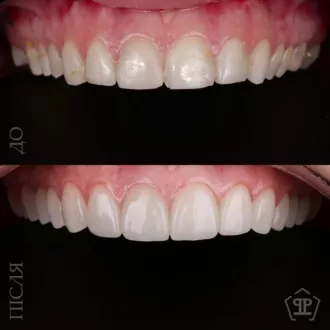

Произведено: диагностику, цифровую планировку улыбки, моделирование формы зубов, минимально инвазивную подготовку, установку керамических реставраций E-max. Результат: гармоничная форма зубов, естественный цвет и прозрачность, правильная длина резцов, более открытая и выразительная улыбка с сохранением собственных тканей зуба.